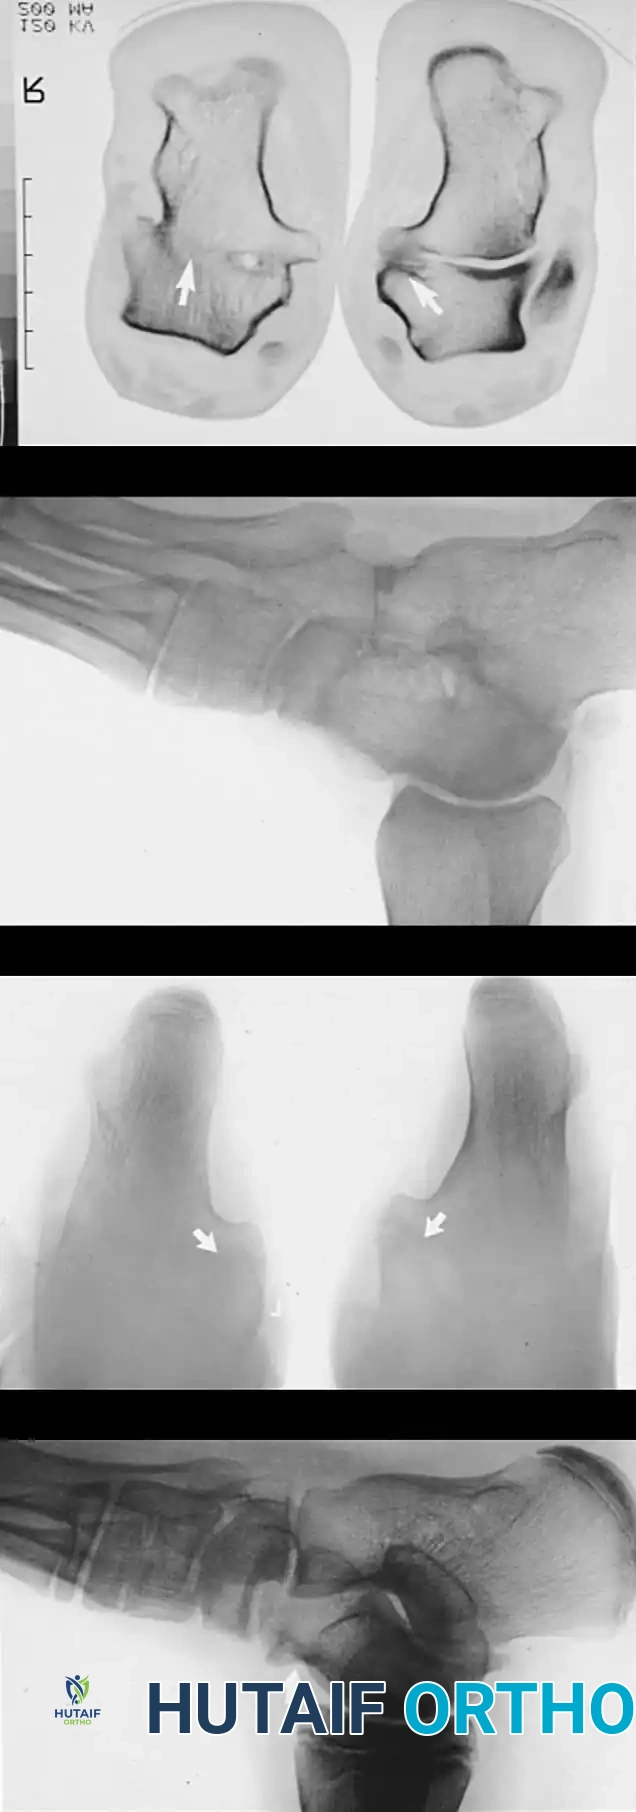

In a parallel study, El Rassi, Riddle, and Kumar evaluated patients presenting with anterolateral hindfoot pain, reduced subtalar mobility, and negative plain radiographs, CT, and MRI. The defining diagnostic feature in their cohort of 19 patients (23 feet) was a positive technetium-99m bone scan, which consistently demonstrated increased radiotracer uptake at the middle facet of the subtalar joint. Surgical exploration revealed a hypervascular, thickened capsule and synovium in this region. Excision of this pathological tissue yielded satisfactory final results in 17 of the 19 patients.

Radiographic Imaging

The 45-degree lateral oblique radiograph is the gold standard for diagnosing a calcaneonavicular coalition. The abnormal bar extends from the anterior process of the calcaneus (just lateral to the anterior facet) dorsally and medially to the lateral/dorsolateral extra-articular surface of the navicular. It typically measures 1 to 2 cm in length and 1 to 1.2 cm in width.

In incomplete coalitions, the adjacent bony margins appear irregular, sclerotic, and indistinct. The talar head may also appear small and underdeveloped.

Radiographic Pearl: The "Pseudocoalition"

In older adolescents and adults, a prominent anterior tuberosity of the calcaneus may overlap the navicular on standard views, creating the illusion of a coalition (pseudocoalition). This must be correlated with clinical subtalar motion and dynamic fluoroscopy or varied-angle oblique radiographs.

While standard anteroposterior and lateral radiographs may show secondary signs (such as the "anteater nose" sign for calcaneonavicular coalitions or the "C-sign" and talar beaking for talocalcaneal coalitions), advanced imaging is often utilized in modern practice.

Advanced Imaging and Anatomical Reference Gallery

The following images illustrate various presentations, surgical exposures, and advanced imaging modalities (including CT and MRI correlates) utilized in the comprehensive evaluation and treatment of rigid pes planus and tarsal coalitions: